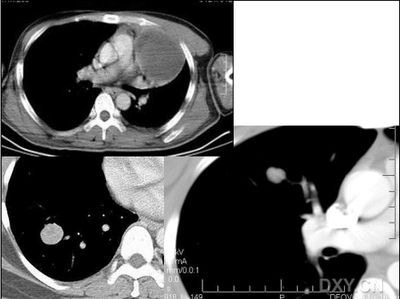

炎性假瘤是肺内某些慢性炎症或慢性炎症的结局所致的肿瘤样病变[3],以肺的增殖性改变为主。一般为机化性肺炎局限化的结果[1,4,5]。其大体形态为肺实质内的球形肿块,压迫周围肺组织形成假包膜。病人大多有急性或慢性的肺部感然症状,约1/3的病人无临床症状,或症状轻微,多数仅有胸痛、胸闷、干咳;少数患者有痰带血丝。一般无发烧。组织学特征为多种细胞成份组成的肉牙肿。根据细胞及间质成份的不同,可分为多种组织类型,纤维组织细胞瘤型、黄色瘤样肉牙肿型、浆细胞肉牙肿型、纤维性黄色瘤型、硬化性血管瘤型、假性淋巴瘤型及肺泡上皮增生型等。

(1)圆型、类圆型,边缘光滑的肿块。多单发,大小约3-5cm,密度均匀,边缘光滑锐利。多无分叶,偶有小切迹,肿块周围可有粗长条素血管纹理或棘状突起。

(2)局限性胸膜粘连肥厚。炎性假瘤大多位于肺的周变部,邻近胸膜常出现炎性反应。部分可显示肿块胸膜缘(包括叶间胸膜)有尖角样粘连带。

(3)增强扫描显著强化。部份病栽内可见边界清楚的低密度坏死区。

炎性假瘤:病灶可呈圆形、椭圆形、三角形、亚铃形等,边缘多比较光滑,密度呈中或偏高密度,周围可有不规则条索影,周围一般无周围充血征象。肿块内可有空洞,可有钙化,但多密度均匀。假性淋巴瘤型可见支气管气相,多为单发,少见多发。肿瘤生长慢,可持续十余年,抗炎可有效果,但阴影不易消散。